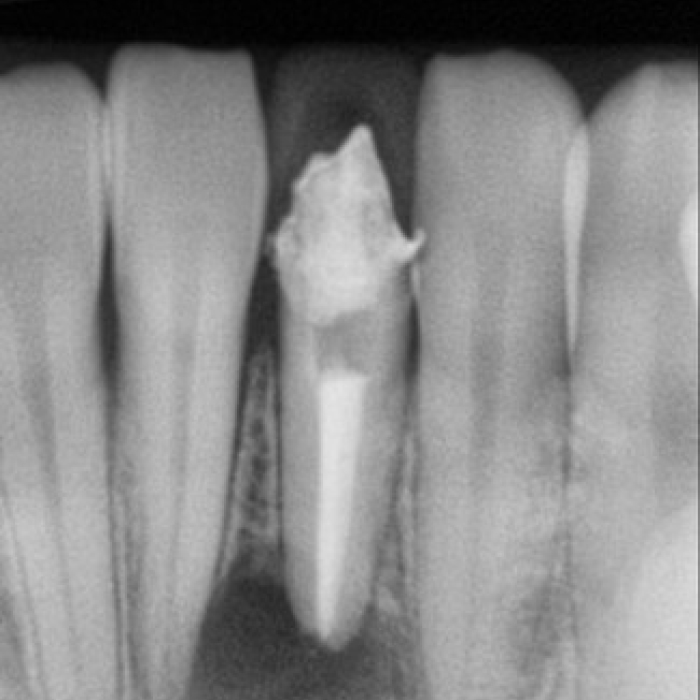

신경치료 전후 사례

• 치료 전

치료 후

• 치료전

치료후